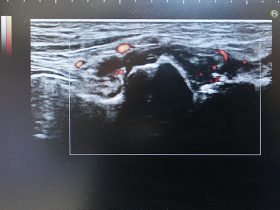

超音波検査(エコー)

近年目覚ましく性能の向上している超音波診断装置を聴診器代わりに用いて診療の様々な場面に役立てています。

レントゲンでは問題がない場合も、さらに一歩進んだ病変の評価や観察が可能となりました。

視診や触診、レントゲンだけでは判断しづらい病変の観察が簡便に行えます。

病変部周囲を動かしながら画像評価が行えるのも大きなメリットとなります。

炎症や出血の拡がりや改善の程度を痛みを伴わず評価できます。